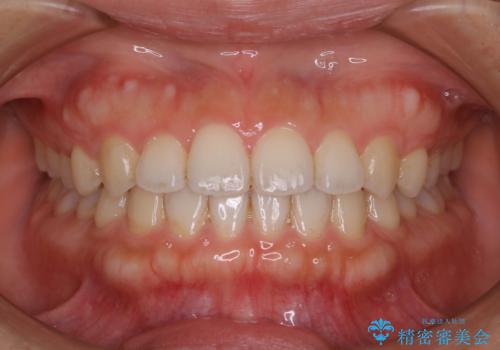

- 歯科がかなり久しぶりで、今後虫歯治療予定のためまずはクリーニングを希望されました。PMTC60分コースを行いました。

CRは経年的劣化や、着色してしまうことがあります。PMTCでクリーニングを行うと、古いCRが目立つことがあるため、気になる際は詰め替えを行います。

また、治療が開始される前などにも、全体的にクリーニングを行いご自身本来の歯の色、状態を精密に確認することが大切です。